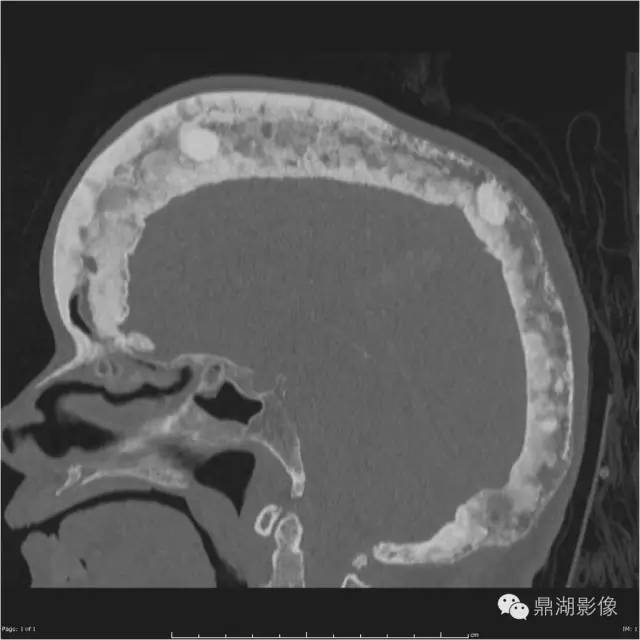

棉絮征—佩吉特骨病

棉絮征

今天下班回家的路上看到一个买棉花糖(Cotton candy)的摊子,回来的时候就想到写一下“Cotton wool”这个征象,典型的棉绒征在国内应该不算常见,今天讲到的棉絮征是Paget(佩吉特)骨病中局限性钙质沉着在疏松的颅骨骨质中呈类似棉絮样改变的征象。

影像特点

随着时间的推移病变可发生变化,治疗后溶骨区域可逆转。则某些特殊区域佩吉特骨病可出现特征性的改变,如脊柱受累时可出现“窗户框”现象,骨盆受累时可出现髋臼内陷及骶髂关节关节强直,颅骨受累时可出现骨质疏松性局限性钙质沉着和颅底凹陷症。

MR、CT 有助于评估脊柱、骨盆、颅骨的佩吉特病变及恶变的情况,PET 则可评估有恶变倾向的病灶。当影像学诊断存在困难或者怀疑佩吉特病有肉瘤变时则需要行穿刺活检。